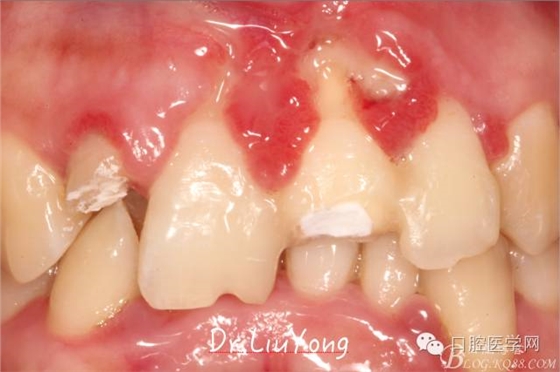

術(shù)后兩周復(fù)查,牙齦紅腫明顯好轉(zhuǎn),探診不出血,但是此時(shí)A1唇側(cè)牙齦角形退縮1.5mm,B1唇側(cè)牙齦退縮3.5mm,B1遠(yuǎn)中牙齦乳頭萎縮明顯,B2近中牙齦萎縮約1mm,且A1B1B2牙齦退縮處角化牙齦幾乎缺失,同時(shí)上唇系帶直接牽拉于B1齦緣。患者為高笑線女性,露齦笑,由于存在前牙區(qū)牙齦的高度嚴(yán)重不對(duì)稱及前牙牙冠過(guò)長(zhǎng)的問(wèn)題,因此嘗試通過(guò)膜齦手術(shù)改善患牙牙齦退縮。通過(guò)術(shù)前分析,A1唇側(cè)牙齦退縮屬于Miller分類第一類, B1唇側(cè)牙齦退縮屬于Miller分類第3類(B1遠(yuǎn)中牙齦乳頭為2類,Nordland and Tarnow分類法),B2唇側(cè)牙齦退縮屬于Miller分類第3類,由于擬采用冠向復(fù)位瓣的方式治療牙齦退縮,因此需要先行上唇系帶修整術(shù),解除上唇系帶帶來(lái)的過(guò)大牽引力。

潔治刮治后2周,如上圖